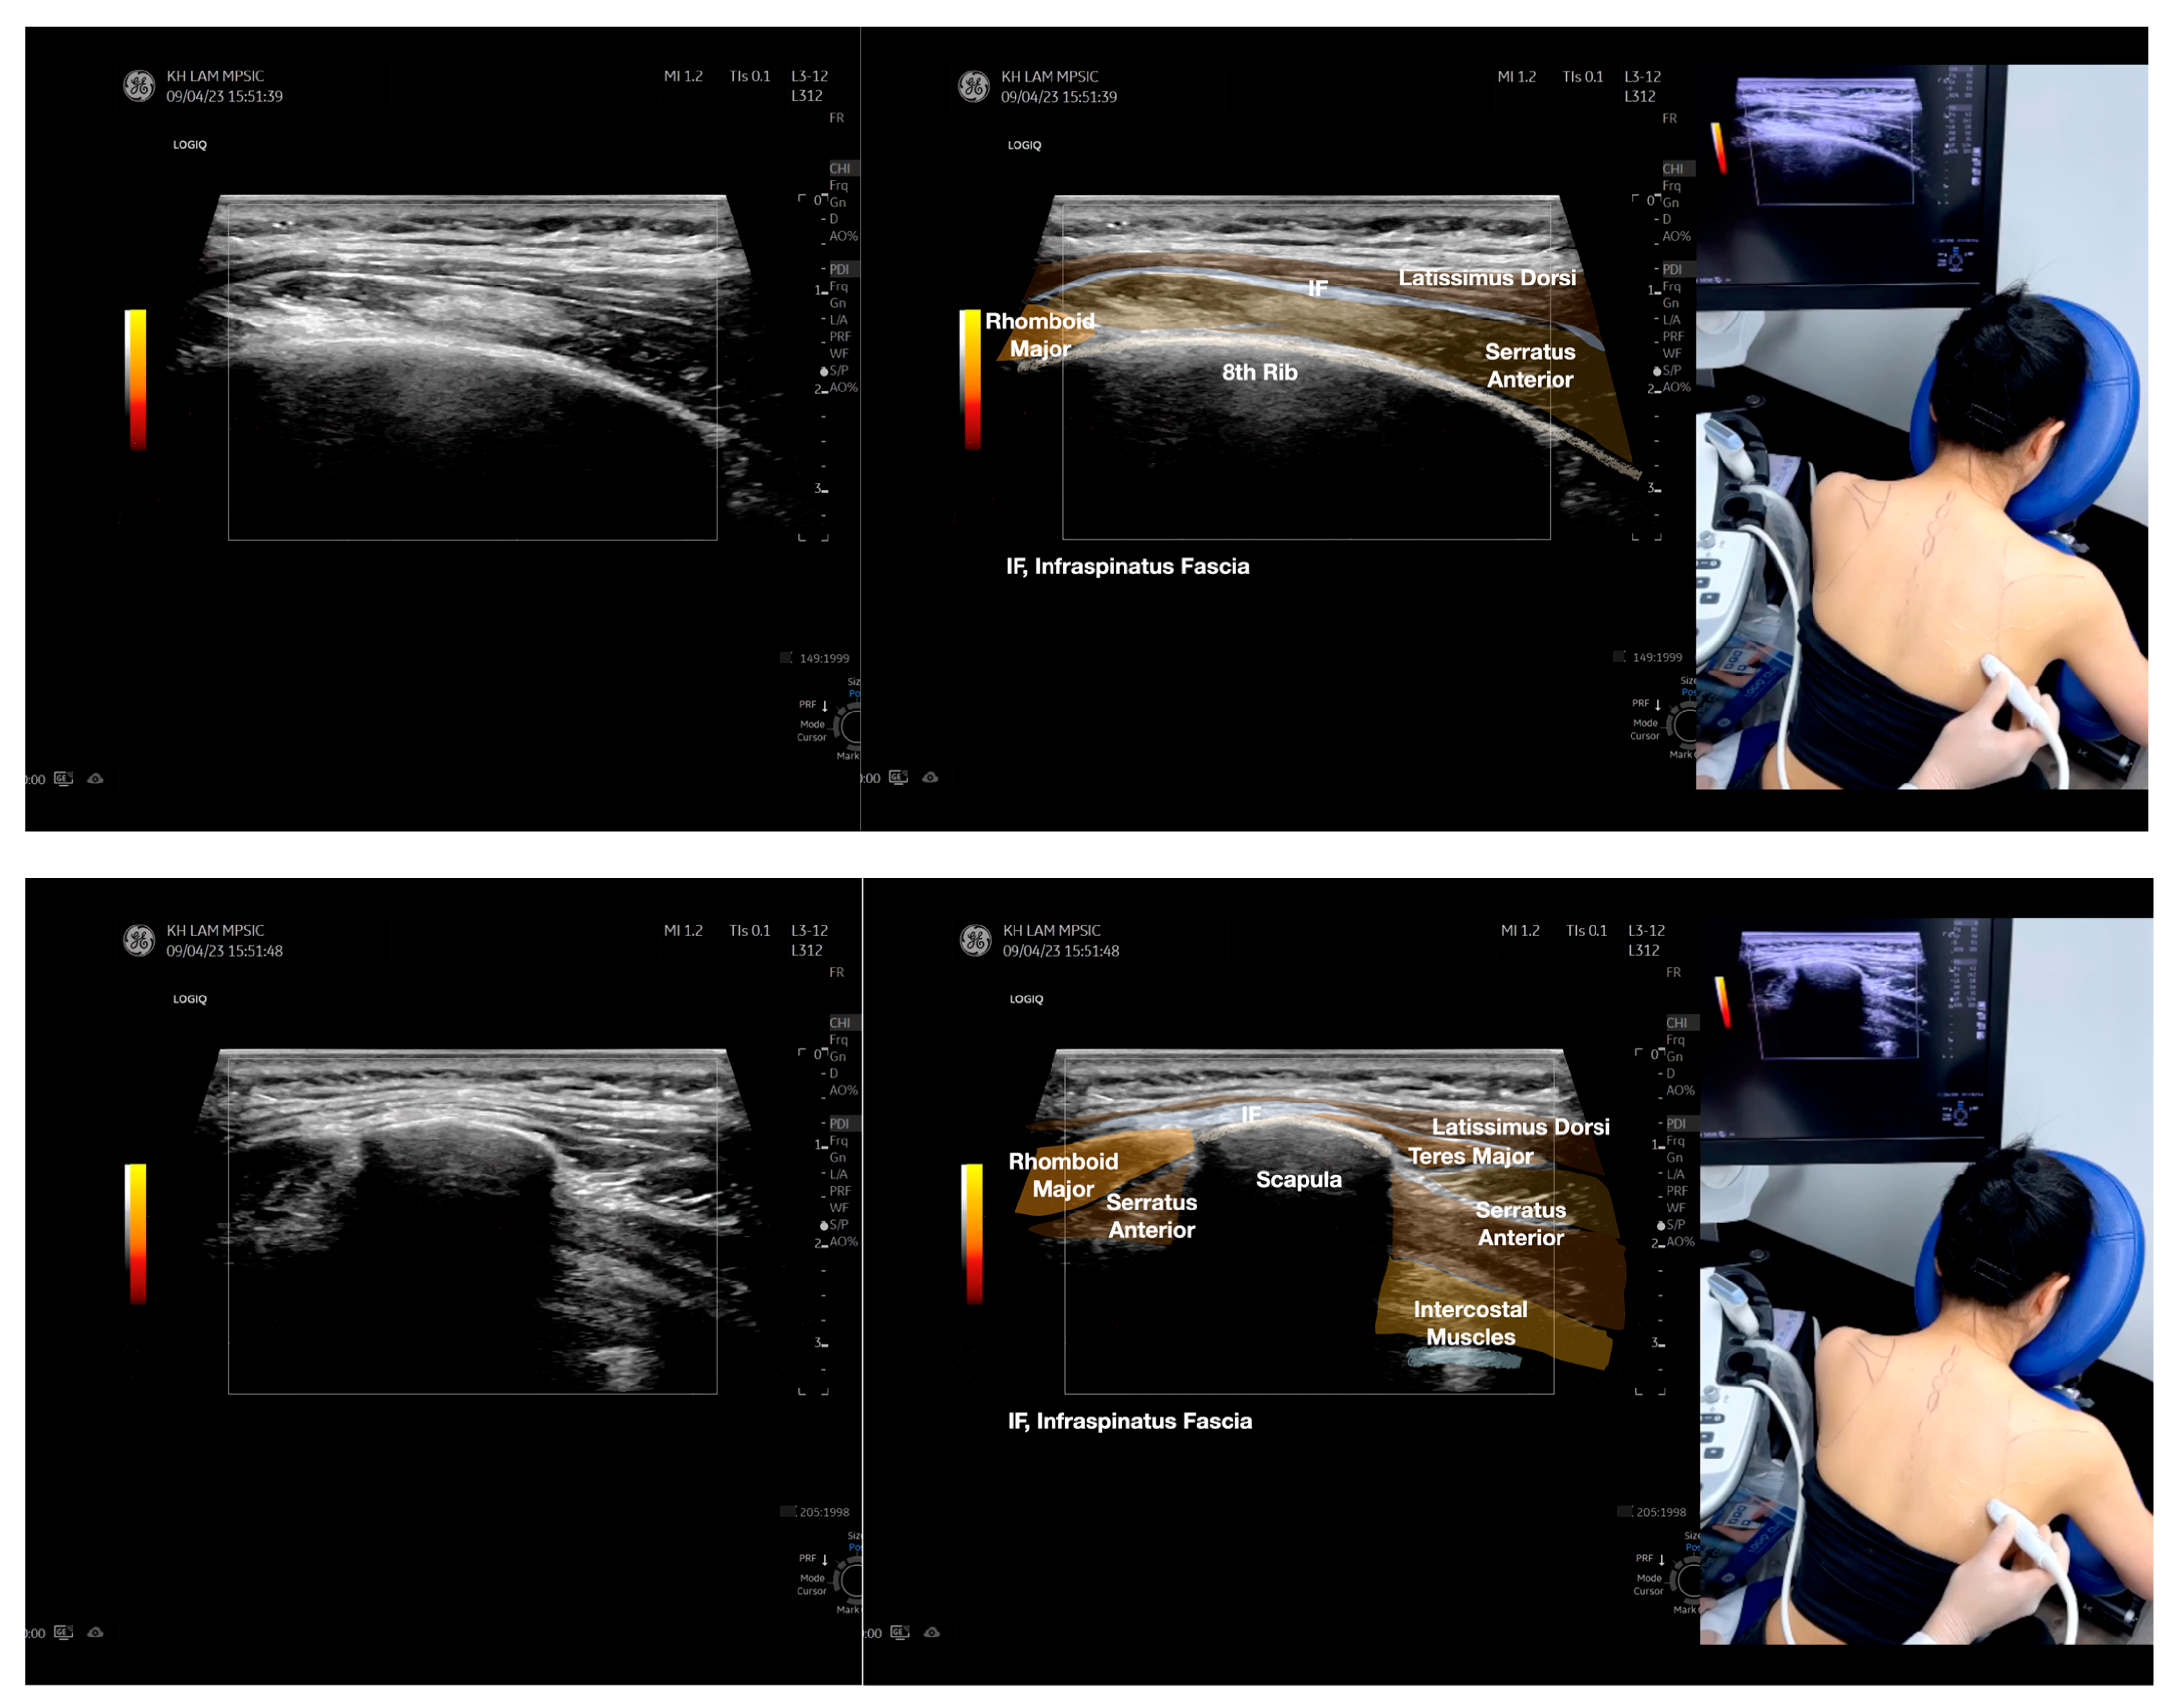

Figure 4.

Sonoanatomy of the medial edge of the scapula, its related muscles, and the infraspinatus fascia. The step-by-step scanning techniques of these structures illustrated in this figure have been shown in Video S8. Available online: https://www.dropbox.com/s/iaej3rxhl83kqt4/Figure%204.docx?dl=0 (accessed on 1 January 2023).